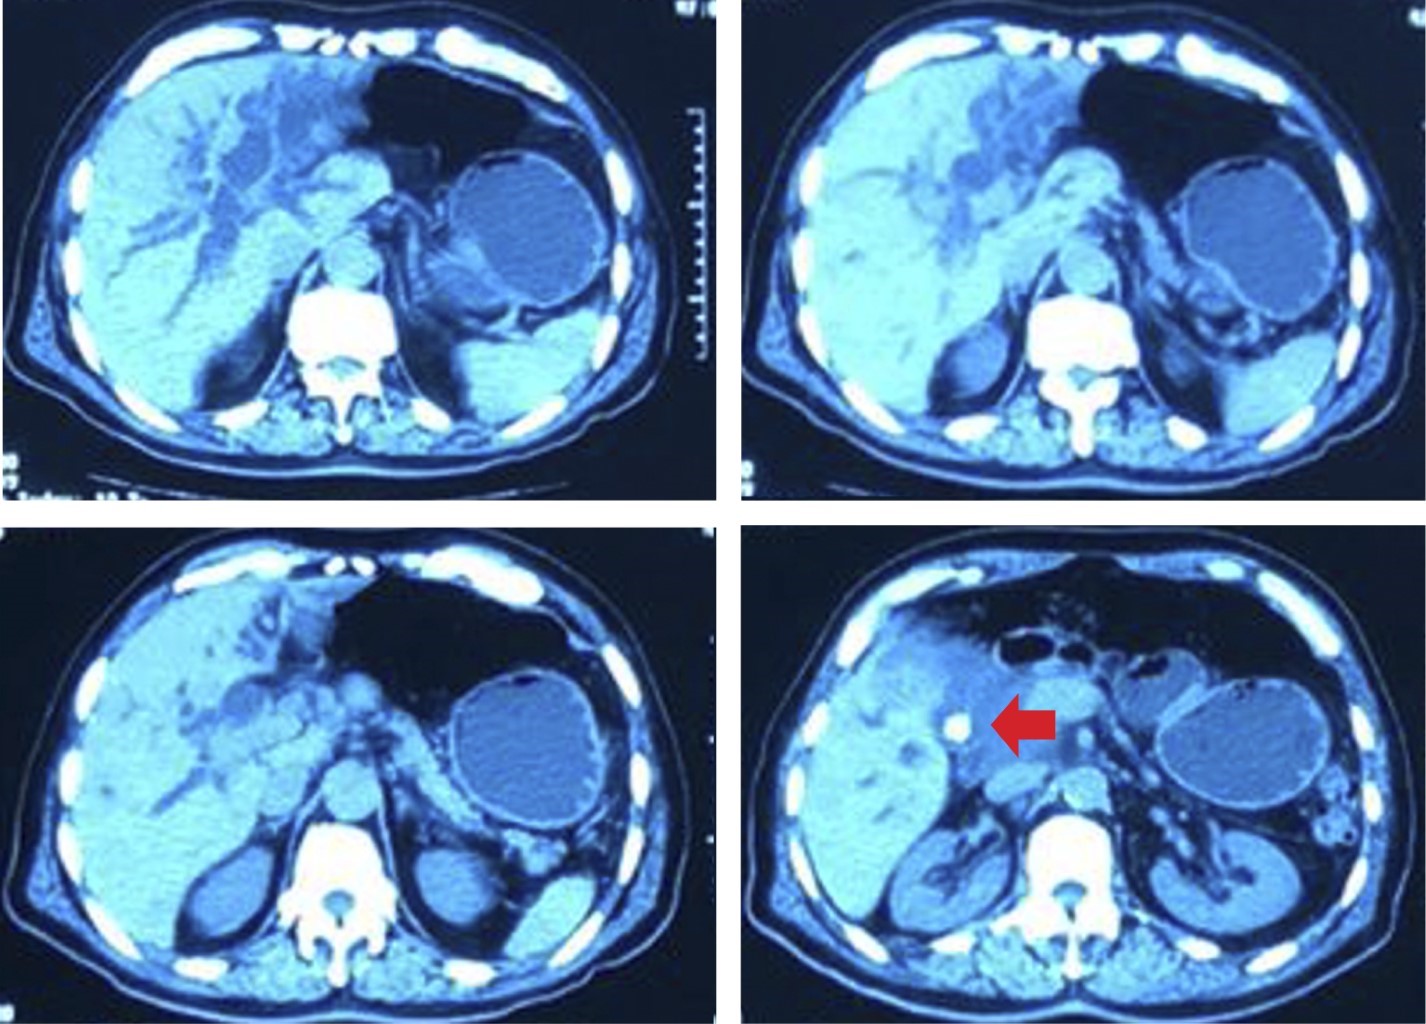

Se realiza tomografía computarizada axial contrastada de abdomen encontrando importante dilatación de la vía biliar intra y extrahepática con colédoco de 19 mm, litiasis vesicular, así como engrosamiento de la porción intramural del colédoco distal, sin observar defectos de llenado. El páncreas se aprecia de contornos regulares sin colecciones ni modificación de la grasa peripancreática. Cabe mencionar la presencia de adenomegalias del segmento retroduodenal no mayores a 8 mm (Figura 1).

Figura 1